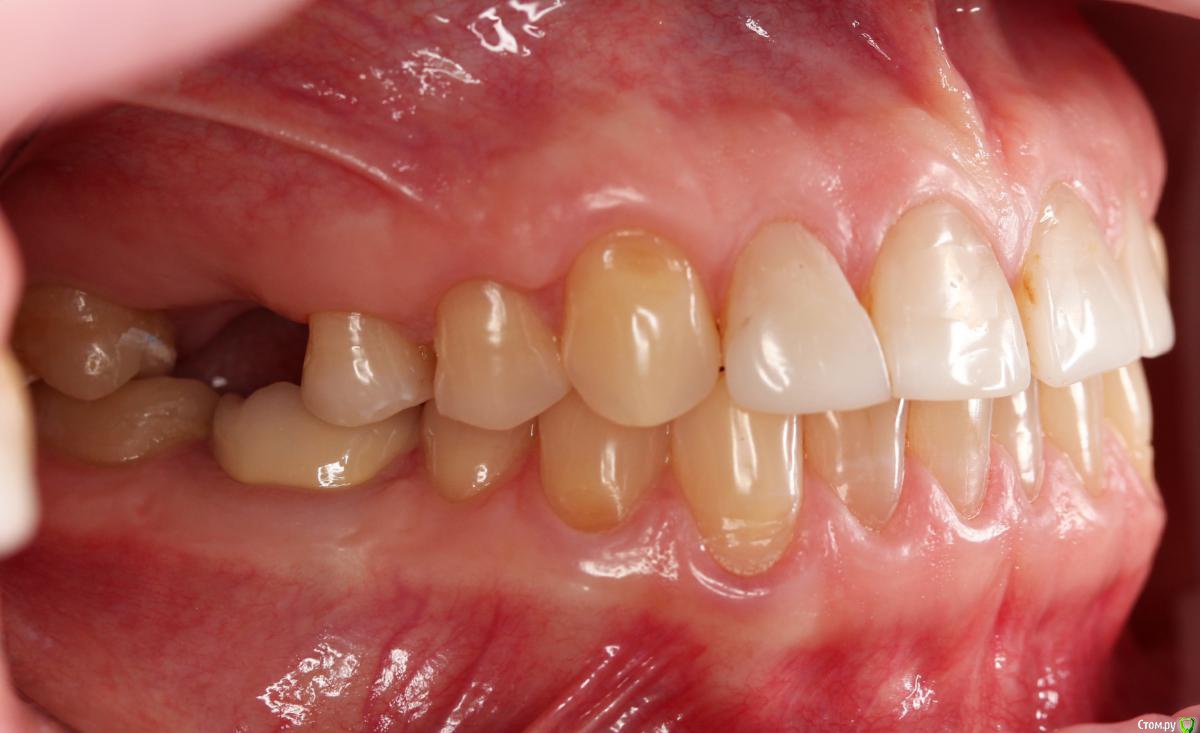

Dmitry DK Опубликовано 10 сентября, 2019 Поделиться Опубликовано 10 сентября, 2019 Фотопротокол к сожалению не полный, но ничего особенного и не проводилось. 1) Открытый синус, удален пломбировочный материал из пазухи, уложен 1 г Bio-oss 2) через 6 мес имплантация Straumann SP 4.1\10 Результат через год 9 Ссылка на комментарий

Irouil Опубликовано 10 сентября, 2019 Поделиться Опубликовано 10 сентября, 2019 Классный результат, только я бы не разделял хирургические этапы 1 Ссылка на комментарий